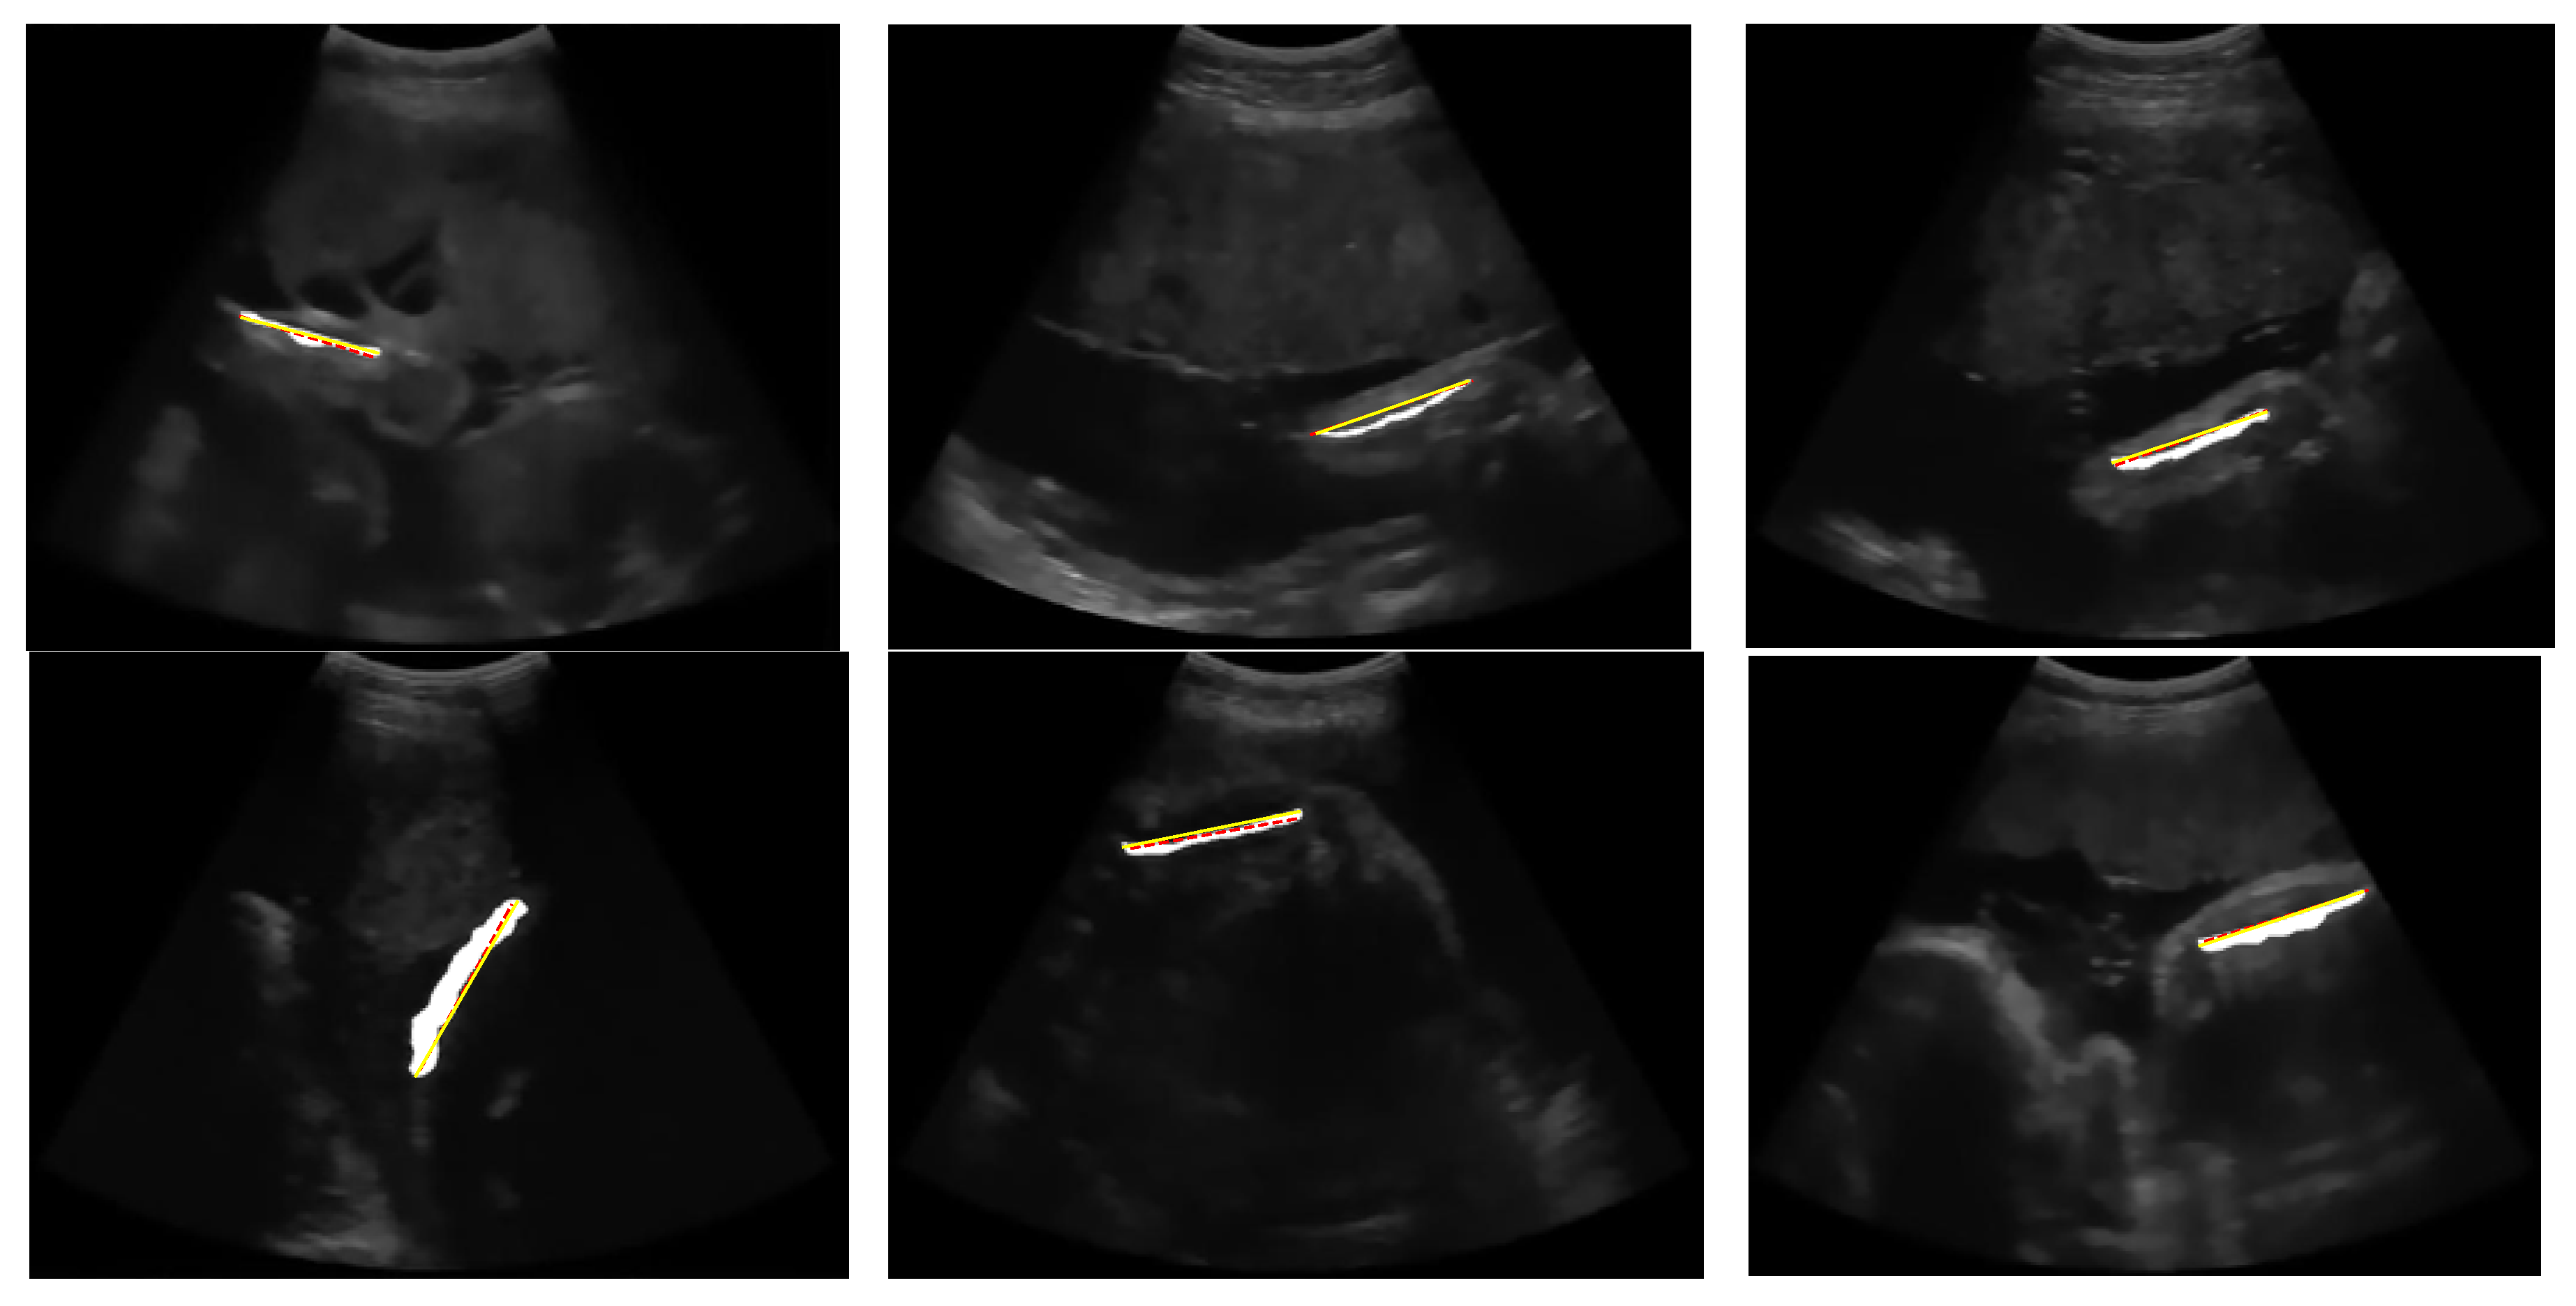

Using the dataset in this research, the performance of the proposed thresholding method is compared with the approaches proposed in previous studies, with some modifications in the object selection stage. In particular, for the entropy-based thresholding method which produces a small object, we do not utilise the object selection step. For the multilevel Otsu thresholding method and the statistical-based thresholding method, large objects with areas larger than 1,4% of image size pixels are not cut out because the thresholding results tend to be broader objects. However, the objects attached to the edge of the image were removed. Figure 21 shows the outcome of the segmentation and measurement of the FL for each image in Figure 2. After the region was obtained, FL was measured based on the line length.

Figure 21. The result of the automatic FL segmentation and measurement where the white region is a femur area, the red line is ground truth of FL, and the yellow line is the detected FL.